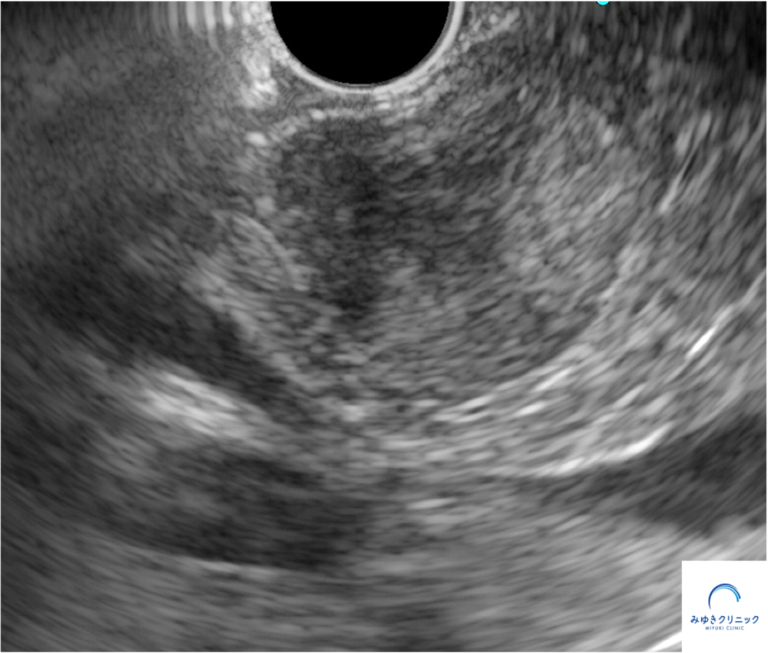

当院で施行した超音波内視鏡検査では、膵頭部に18X22mmの腫瘍を認め、内部には高エコー部(出血を反映)と低エコー部(嚢胞)が混在していました。

<超音波内視鏡>

引きつづき超音波内視鏡下穿刺診をおこないました。

採取した検体の免疫染色の結果(β-catenin陽性、synaptophysin一部陽性、chromogranin A陰性)から、膵充実性偽乳頭腫瘍と診断しました。